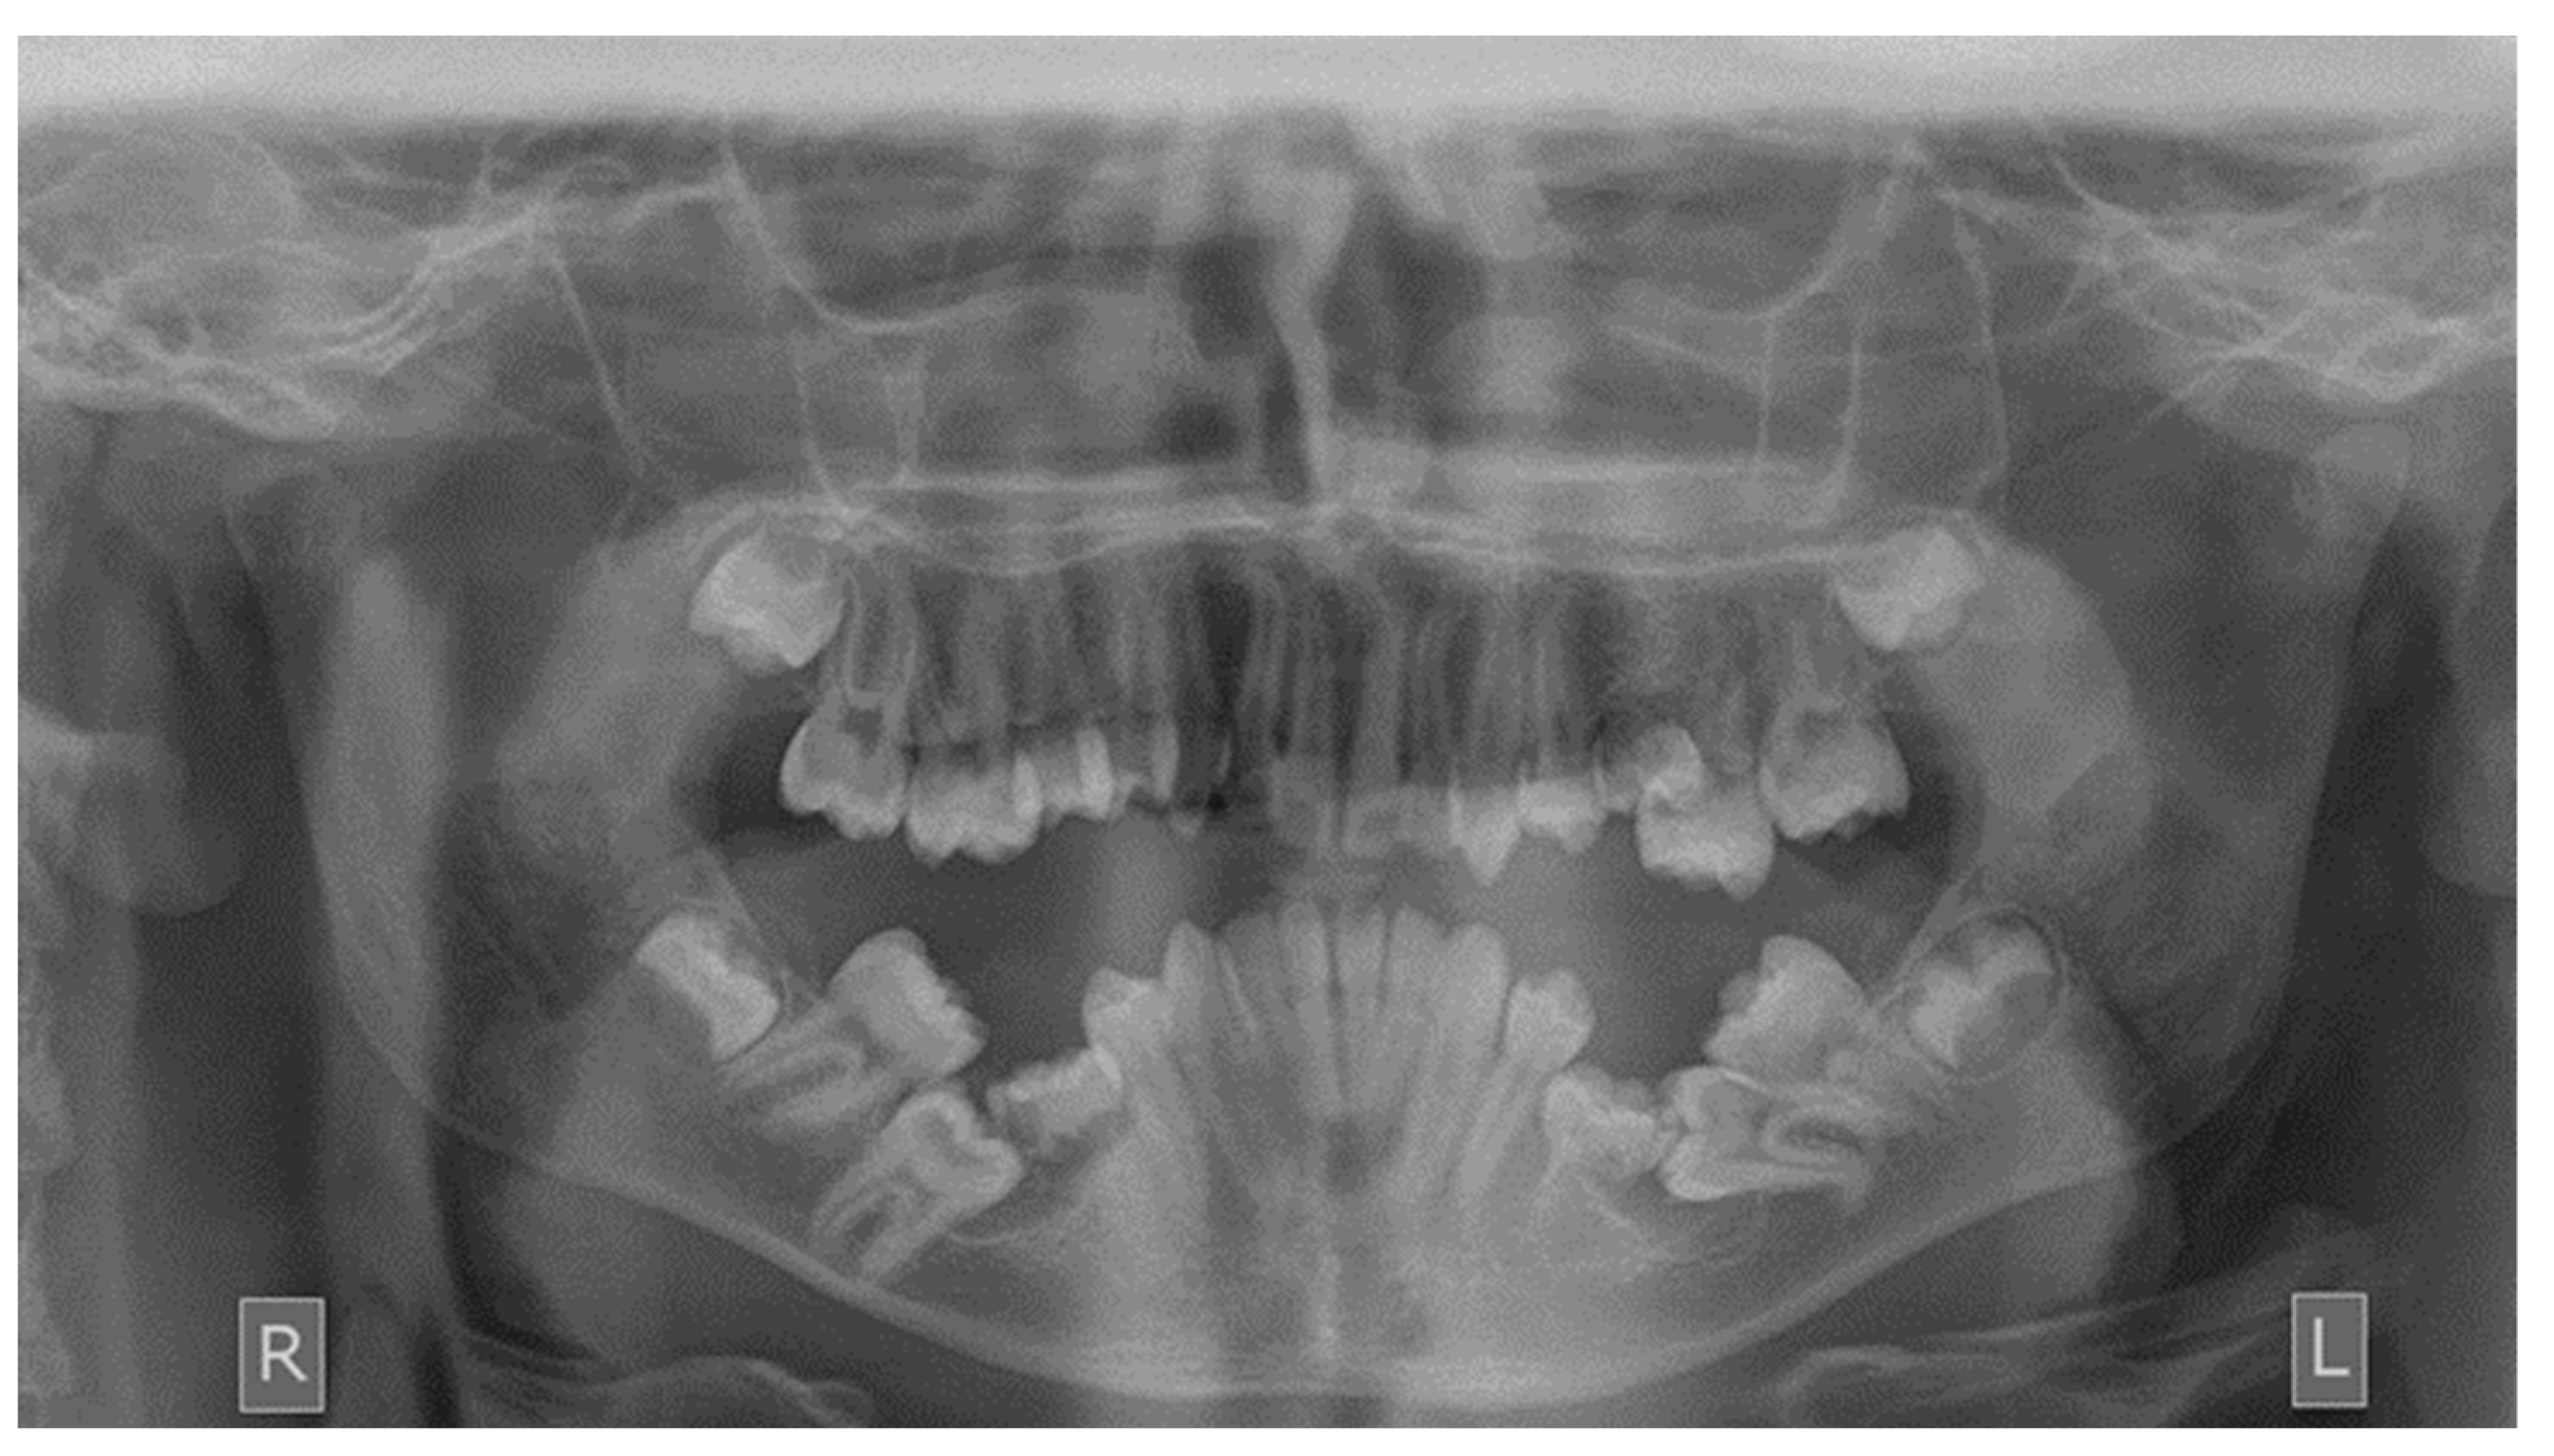

As far as the etiology of impaction is concerned, 205 patients presented one factor responsible for impaction, while 7 presented two. Table 2 shows the ectopic eruption path as the most frequent factor that was reported in 5.29% of total patients examined and mostly reported in maxillary canines. The next most common etiology was the loss of space in the arch (2.50%), followed by the ankylosis of deciduous teeth (1.71%). Concerning the rest of the causative factors, supernumerary teeth other than deciduous were observed in 1.29% of the patients, while the mesiodens was the most frequent supernumerary permanent tooth. In total, 1.21% of the sample presented tumors such as odontoma and osteoma, more often in association with maxillary central incisors. Supernumerary deciduous teeth affected 0.86% of the patients examined, while the ankylosis of permanent teeth was presented in 0.79 of the cases. The maxillary second premolars were the most frequently impacted teeth due to ankylosis. The least common etiology of impaction proved to be the primary failure of eruption, with 3 reported cases out of 212 patients, that following the radiographic examination were all confirmed by genetic tests. Panoramic radiographs indicated for some local etiological factors are presented below (Figure 1, Figure 2, Figure 3 and Figure 4).

Figure 2. Impacted first mandibular molars.